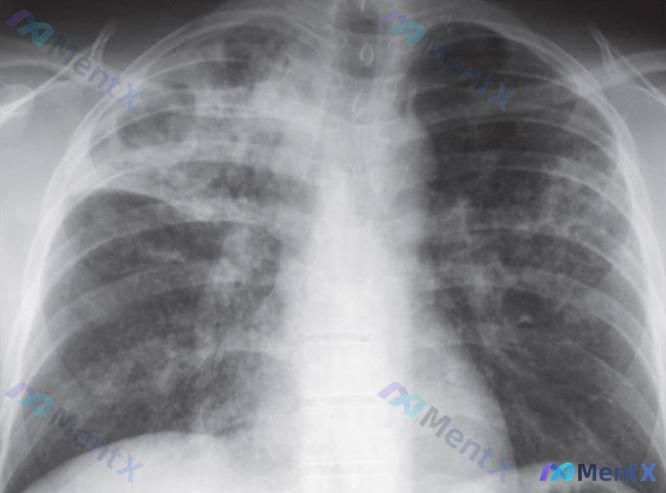

整理了一个挺有警示意义的病例,这个“临床-影像分离”的坑真的很容易踩,分享一下思路: 病例基本情况 - 患者:27岁女性,HIV感染 - 主诉:2周疲劳、发热、干咳,轻微活动即严重疲劳 - 生命体征:T 103.2°F,HR 84bpm,BP 116/72mmHg,RR 19bpm - 体征:双肺底...